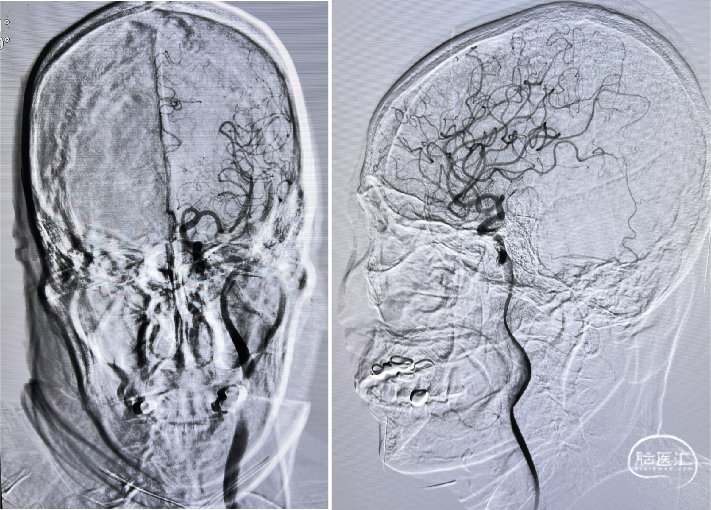

术后RICA造影 :mTICI 3级。

Reexamination Cranial CT:梗死区造影剂渗出。

Reexamination Cranial MRA。

Reexamination Cranial DWI:无明显的血栓向远端逃逸或小血栓脱落后新形成的皮层或分水岭点片状梗死。

Reexamination Cranial T2 Flair。

Reexamination Cranial SWI:壳核后部,造影剂渗出最多的地方再灌注损伤。